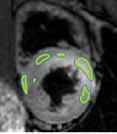

4.2 Visual assessment

We select the case that achieves the highest and lowest dice score for visual assessment. Fig. 4 shows example segmentation results where the proposed method achieved the highest agreement with the ground truth delineations. Fig. 5 shows example segmentation results where the proposed method achieved the lowest agreement with the ground truth delineations.

| (a) LV BG | (b) RV BG | (c) LV NM | (d) LV ME | (e) LV MS |